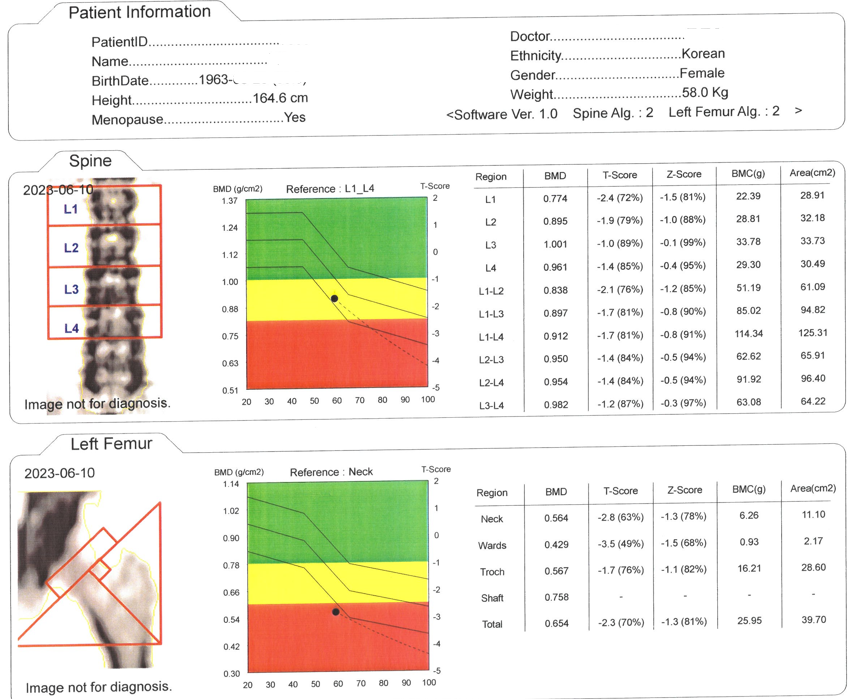

23³â 6¿ù 10ÀÏ °ñ´Ù°øÁõ Áø´Ü¾à 6°³¿ù Æò¾È»ê°ñ»ê º¹¿ë ÈÄ23³â 12¿ù 23ÀÏ °ËÁø °ñ¹Ðµµ °³¼± °á°úÀÚÇâ¿ä¾çº´¿ø Àç¿øÈ¯ÀÚ°¡ ¾à 6°³¿ù Æò¾È»ê°ñ»ê º¹¿ë Èİñ¹Ðµµ °Ë»ç ÈÄ ¼öÄ¡ÀûÀ¸·Î ¿ÏÈ µÈ °Ë»çÁö ÀÔ´Ï´Ù.°ñ´Ù°øÁõÀ» °Þ°í °è½Å ºÐµéÀÌ °è½Ã´Ù¸é ÀÚÇâ¿ä¾çº´¿øÀ¸·Î ¹®ÀÇÁֽñ⠹ٶø´Ï´Ù.¿Ü·¡, Àç¿ø ȯÀÚ Áø·á ÈÄ Æò¾È»ê°ñ»ê ó¹æÀÌ °¡´ÉÇÕ´Ï´Ù.1661-8927